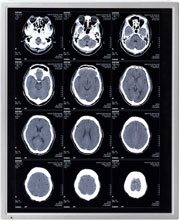

NEC LCD Technologies Announce New 19-Inch Monochrome LCD Module for Medical Use

NEC LCD Technologies today announced that in mid-October it will begin shipping samples of its new 19" (48cm) monochrome SXGA, amorphous silicon, TFT LCD module, part number NL128102BM29-05A, which is suitable for use in the medical field. This module features NEC LCD Technologies' proprietary SA-SFT technology, which boasts an ultra-wide viewing angle of 170 degrees, high luminance of 1000cd/m2 and a high contrast ratio of 900:1, and high-grade greyscale performance (each pixel consists of three sub-pixels, and each sub-pixel controls 256 greyscales individually, resulting in the display of 766 greyscales simultaneously by each pixel).